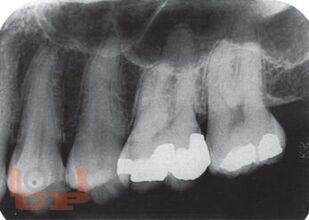

В уникальном компактном руководстве под редакцией авторитетного американского автора детально рассмотрены все основные разделы практической стоматологии, с точки зрения диагностики и лечения экстренных состояний. В руководство включены также главы о механизмах возникновения и диагностике зубной и оро-фациальной боли, организации неотложной стоматологической помощи в офисе, приложение с прописями лекарственных средств, применяемых в стоматологии. Особый интерес представляет информация о самых современных методах, терминах, технических устройствах и материалах, применяемых стоматологами США.